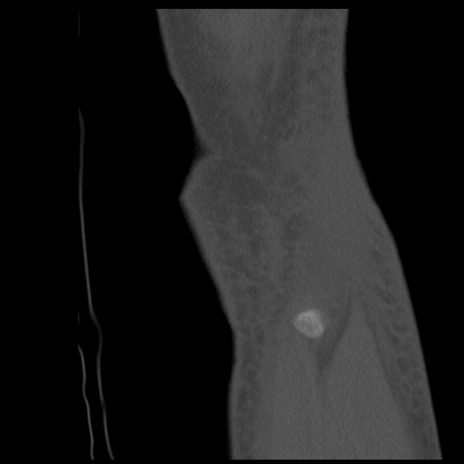

症例28 右膝関節CT(矢状断像)

右膝関節CT